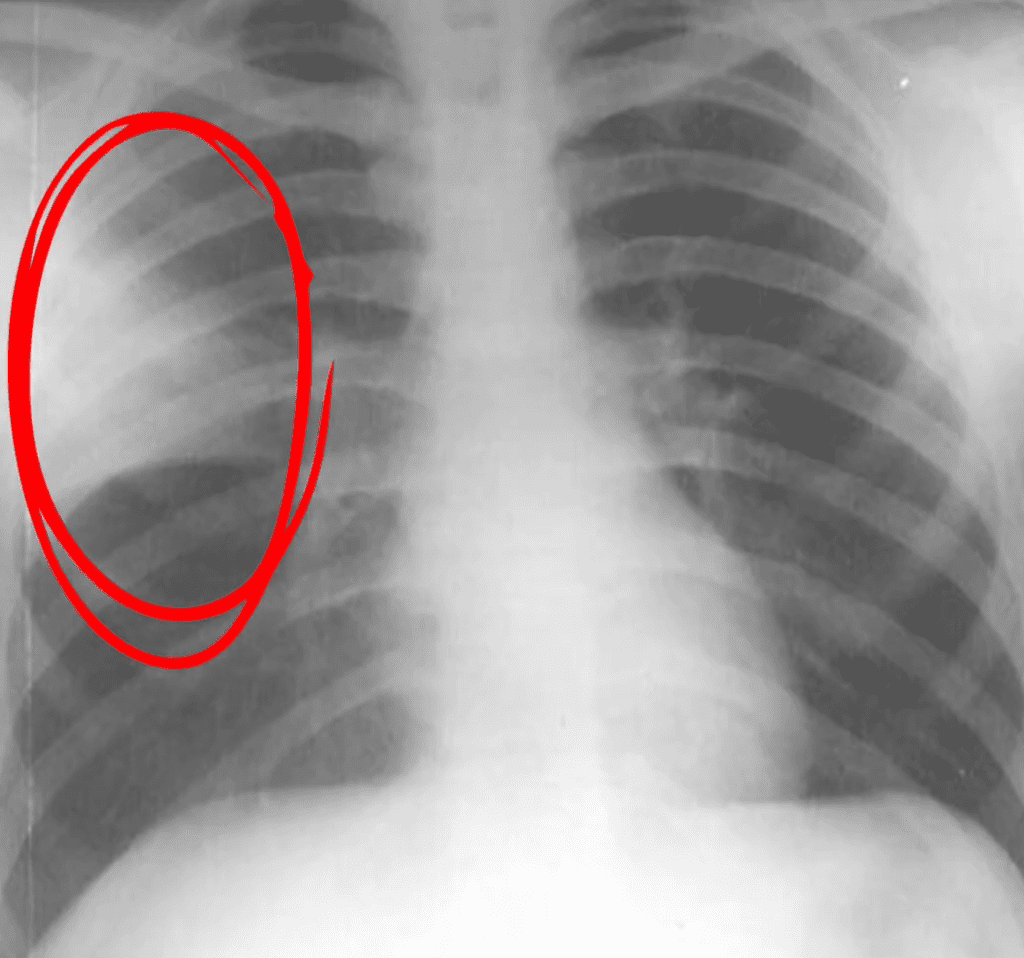

Pneumonia cu condensare

- Deobicei este bacteriană

- Se manifestă prin febră mare, frisoane, stare generală alterată și dificultăți respiratorii semnificative.

- Pe radiografie, apare o zonă albă bine delimitată, ceea ce indică un segment de plămân umplut cu lichid inflamator, unde aerul a fost înlocuit de secreții.

- Aceasta este mai frecventă la copiii peste 2 – 3 ani și necesită tratament antibiotic